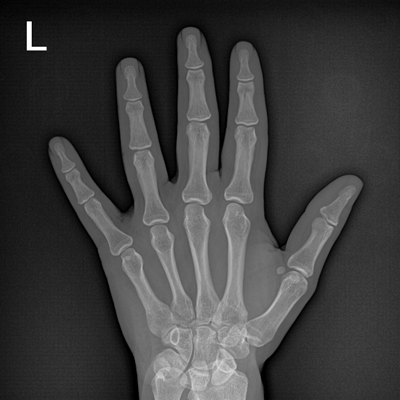

輕量化設(shè)計(jì) 小巧靈活 PLX5100

用于影像科、急診室、病房、ICU、手術(shù)室等多場(chǎng)景應(yīng)用。

● 數(shù)字化無線平板成像,操作簡(jiǎn)便,成像質(zhì)量高